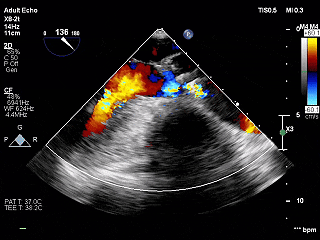

术前超声

主动脉瓣增厚、回声增强,可见钙化,似呈二叶瓣启闭,收缩期开放受限,主动脉腔内射流速度增快,收缩期主动脉腔内前向血流速度峰值4.2米/秒,峰值压差70毫米汞柱,平均速度2.9米/秒,平均压差42毫米汞柱,舒张期瓣膜关闭可。

结论:

-

主动脉瓣二瓣化畸形(Type 0型)

主动脉瓣重度狭窄

升主动脉增宽

室间隔肥厚、左室壁均匀性增厚

左室流出道及左室腔狭窄

TEE长轴:瓣膜深度可

TEE短轴:瓣膜展开良好,仅少量瓣周漏

主瓣峰值流速由术前4.2m/s降至术后1.69m/s

主瓣峰值压差由术前70mmHg降至术后11mmHg